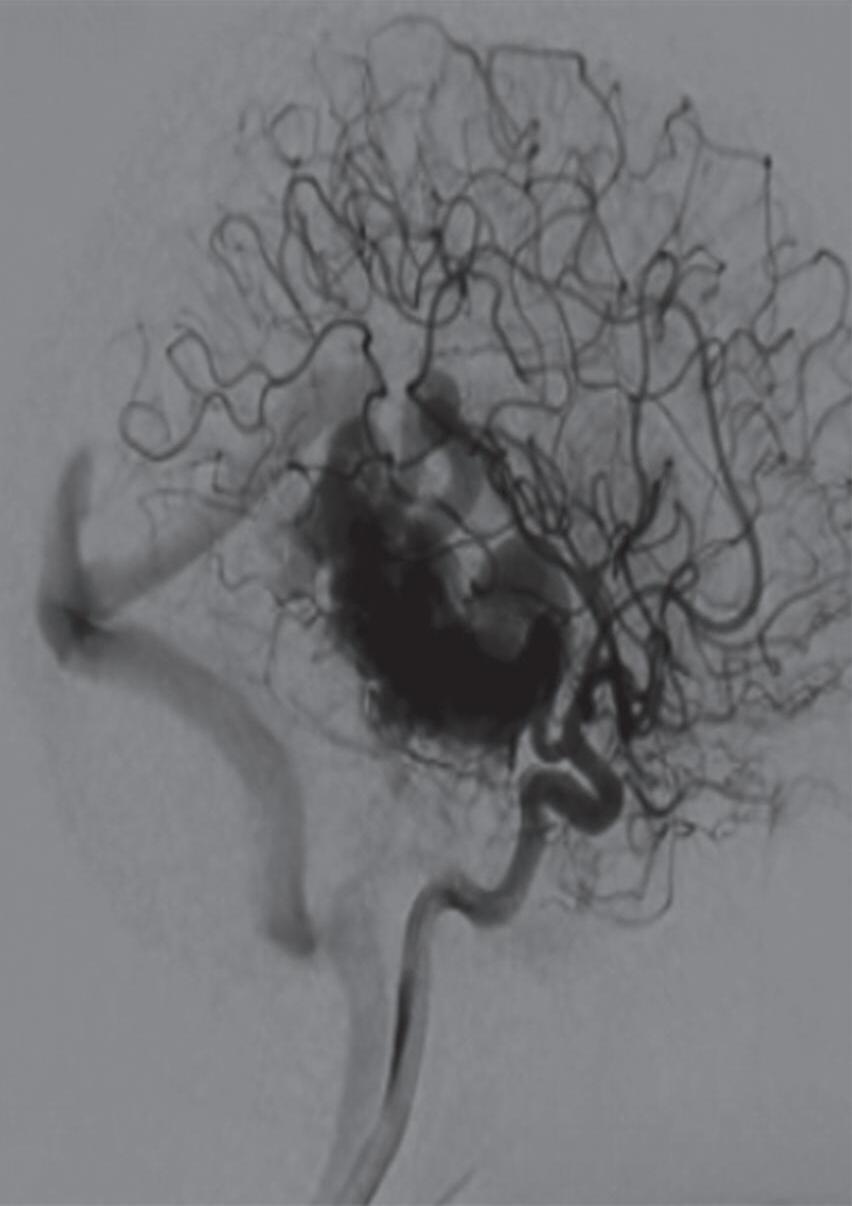

Aproximadamente 18% dos pacientes com MAV têm aneurismas associados, os quais podem ser intra, pré e pós-nidais (Figs. 1-18 a 1-20). A presença de aneurisma, especialmente o intranidal, potencializa o risco de sangramento; estes estão localizados frequentemente nas áreas de alto fluxo sanguíneo, como na topografia das artérias nutridoras da malformação.28,39,40

1-18. (a) RNM T2 corte sagital, (b) arteriografia digital em AP e (c) imagem intraoperatória demonstrando MAV do giro angular esquerdo com aneurisma pré-nidal (setas azuis).

Fig. 1-19. Angiografia pré-operatória em: (a) perfil em fase arterial e (b) venocapilar demonstrando uma MAV no sulco intraparietal direito grau 2, nutrida por ramo da artéria cerebral média e calosa marginal, com drenagem venosa superficial para o seio sagital superior e com aneurisma nidal (setas azuis). (c) Visão intraoperatória do aneurisma intranidal.

Fig. 1-20. RNM T1 com contraste em cortes (a) axial e (b) sagital e (c) FLAIR axial, demonstrando MAV do giro fusiforme esquerdo com presença do aneurisma pós-nidal (setas azuis). Angiografia pré-operatória em (d) AP e (e) em perfil mostrando a MAV anteriormente descrita, nutrida por ramos da artéria cerebral média e posterior esquerda, com drenagem superficial para o seio transverso e sigmoide ipsilateral e aneurisma pós-nidal venoso (setas azuis). (f) Visão intraoperatória do aneurisma pós-nidal (seta azul).